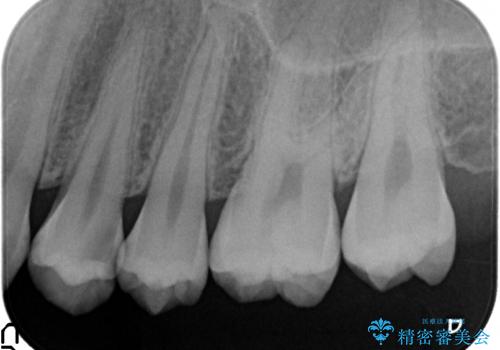

- 左上4番目の歯が欠けてしまったので診て欲しいといらっしゃった方の症例です。

虫歯治療は虫歯の進行度によって処置が変わってきます。

虫歯が小さければ、インレー・クラウン等による修復・補綴処置を行うだけで済みます。

しかし虫歯が大きくなると神経処置や抜歯等をしなければならない場合もあります。

ですので虫歯治療においては早期発見・早期治療が肝要です。